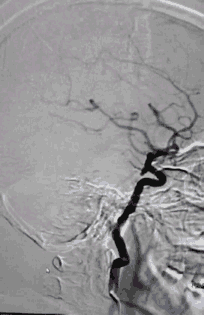

术前影像

栓塞过程

Presgo®微导丝引导支架微导管于基底动脉末端,并预留支架。陆续填塞Jasper®SS弹簧圈4枚,瘤腔填塞致密,撤出支架系统。

术后即刻影像